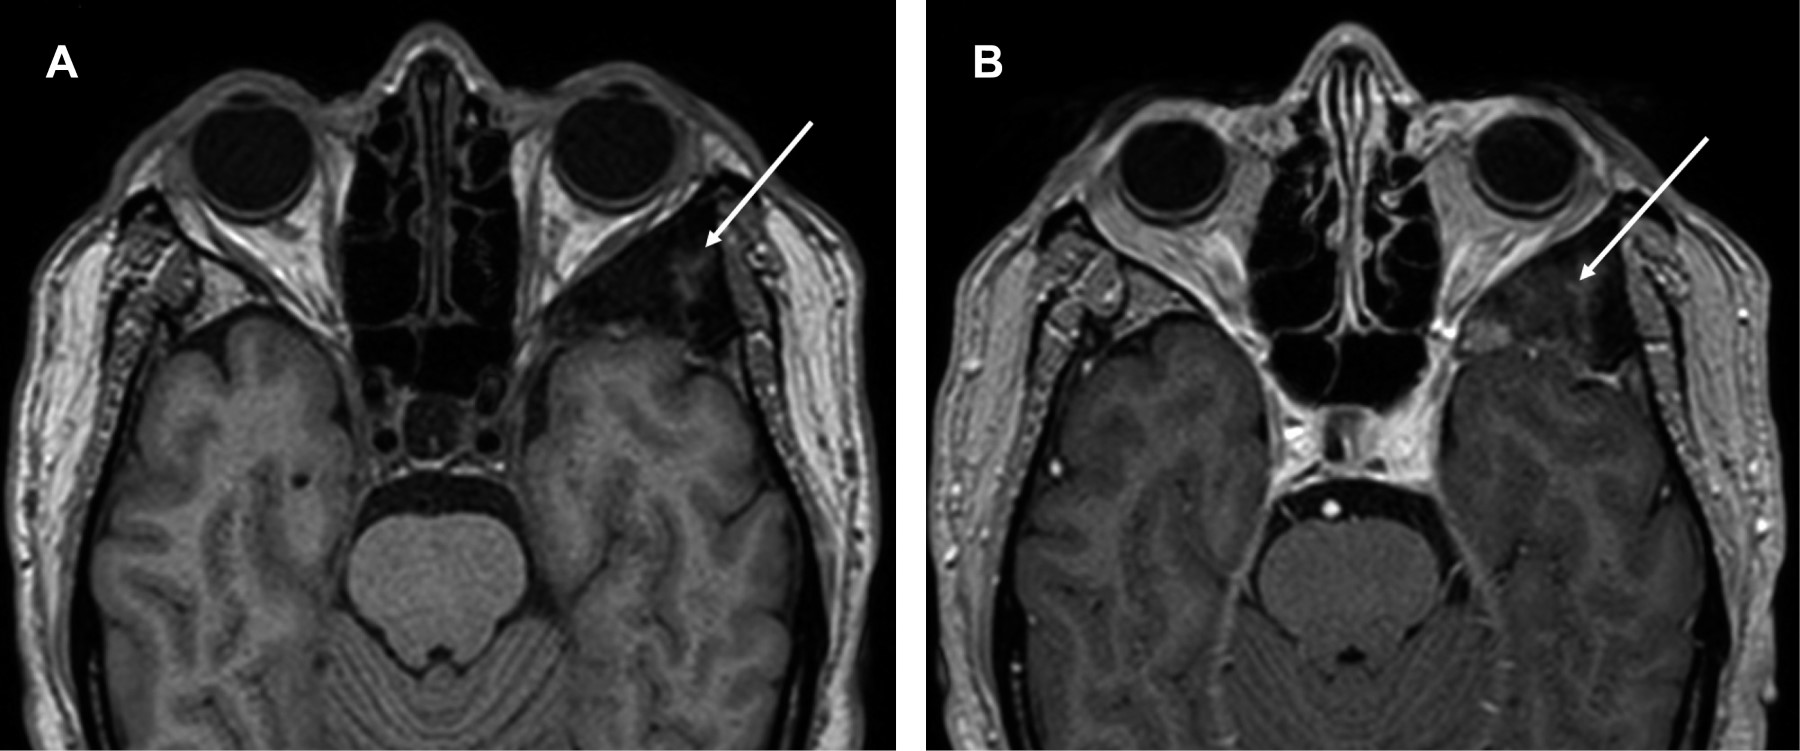

La displasia fibrosa es una alteración esquelética benigna caracterizada por proliferación anormal de tejido fibroso intercalado con tejido óseo de características normales, se observa principalmente en adolescentes y en adultos jóvenes con relación de género 2:1 con predominio en el masculino, suele ser monostótica en 70% de los casos. Se debe a la activación de una mutación somática del gen GNAS1, con sustitución de cisteína o histidina por arginina en la posición 201 de la proteína G, que ocasiona incremento de la actividad de adenilciclasa. En cráneo y cara la frecuencia es de 10-25%. Los exámenes radiológicos y la tomografía computarizada son esenciales para determinar la extensión de la lesión (Figuras 1 y 2).

Figura 1

Figura 2